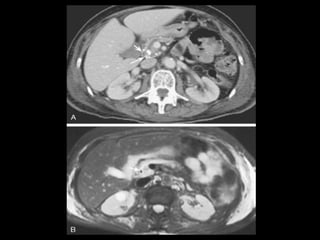

Pseudocistos-TC

Coleção líquida redonda ou oval, com uma parede

fina ou espessa, que apresenta intensificação pelo

contraste;

RM: lesão uniloculada bem definida, hipointensa

em T1 e hiperintensa em T2;

Bolhas de gás: infecção, fístula ou à cistostomia

interna;

Hemorragia aguda dentro do cisto: hiperdensa

Estenose ou oclusão venosa, com formação de

varizes ou pseudoaneurismas.